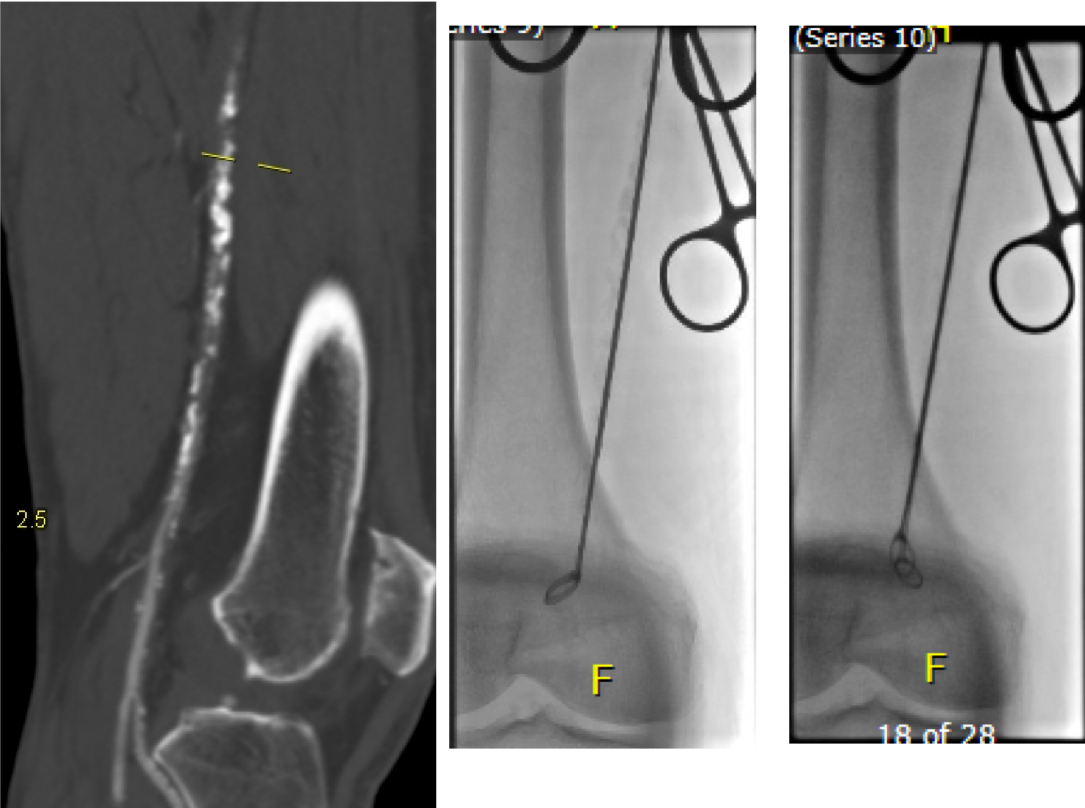

I contacted LeMaitre Vascular and got in touch with your representative, L. Fisher, who promptly sent the Moll Ring Cutters I needed to perform a remote endarterectomy of the patient’s occlusive external iliac and superficial femoral artery plaque. The technical details of remote endarterectomy are have been covered in my blog (https://vascsurg.me/?s=endore), but in the end, through a 7cm incision in the groin (don’t believe the hype, this is minimally invasive), I restored his arteries to their original open condition. Shown below are the results. It was with great sadness that I heard that the LeMaitre Vascular equipment being sent were the last of the stock available in North America. The patient did very well, with the operation completed well before lunch, and is recovering rapidly from his small wound and big rescue. He gets to walk out of the hospital on two legs, but also with the surety that he avoided a major bypass operation, and avoided the short term gains of stenting from the aorta to the profunda -more peel packs and landfill items and a dubious long term durability. Hey, I even used a XenoSure patch on the common femoral.